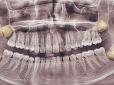

А ви це знали? Чи у всіх людей є зуби мудрості та навіщо вони потрібні

Зуби мудрості, чи треті моляри, традиційно вважаються останнім випробуванням для нашої щелепи. Вони зазвичай з’являються у віці 18–24 років - саме тоді, коли ми вже давно не діти, але ще не готові до стоматологічних хірургічних втручань без емоцій, пер...